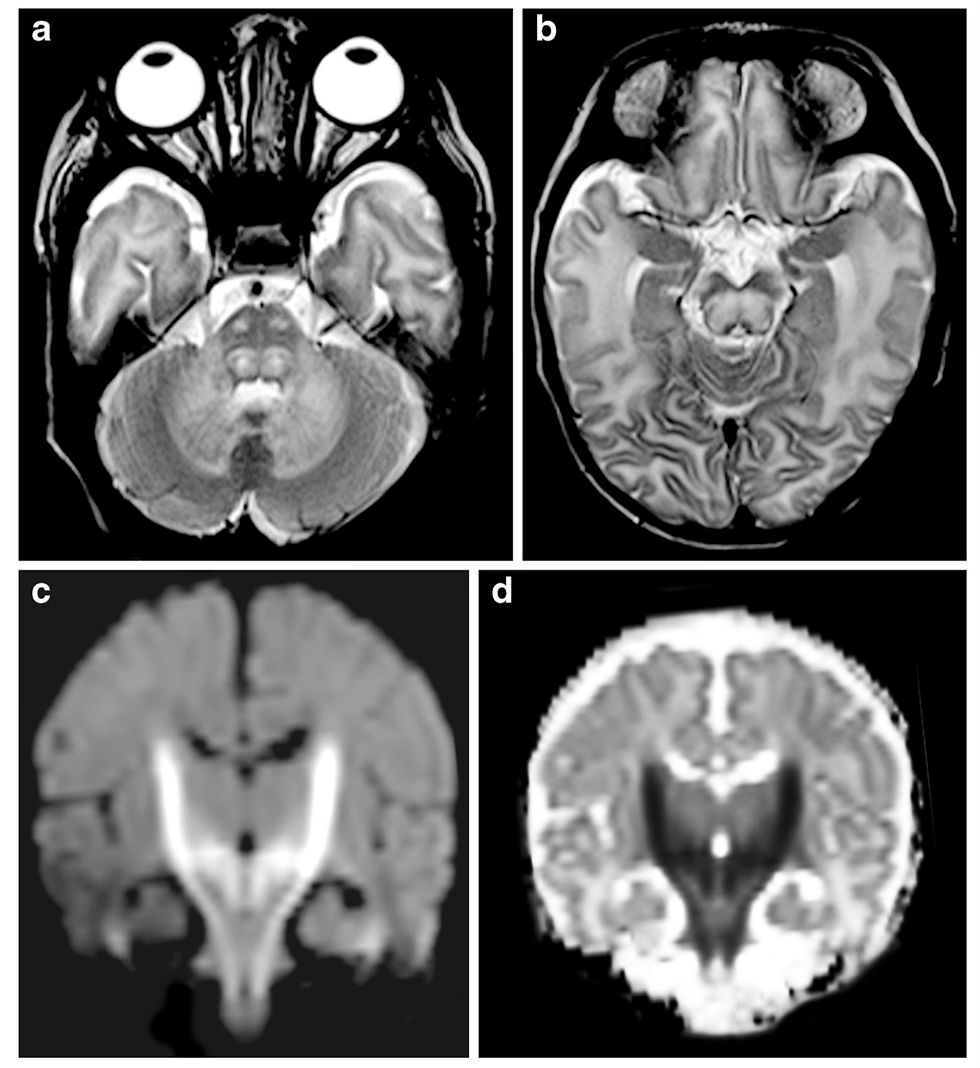

Maple Syrup Urine Disease in a 4-day-old girl.

(N.d.). Researchgate.net. Retrieved July 23, 2024, from https://www.researchgate.net/figure/Striate-injury-and-wide-Sylvian-fissures-in-a-7-month-old-girl-with-a-new-diagnosis-of_fig2_281616841